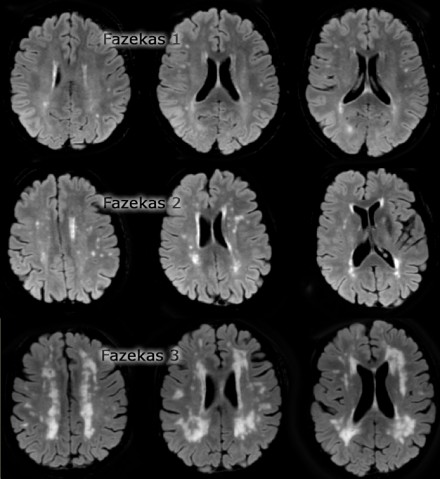

Fazekas等级评分法是目前最常用来诊断脑白质病变和严重的程度。

– 0级: 无病损

– 1级: 存在局灶性病变

– 2级: 出现较大病变

– 3级: 弥散性病变,损伤遍布大脑